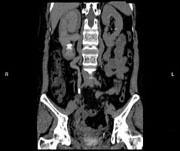

问题 女,44岁,突发性胁腹部绞痛并向会阴部放射伴血尿一次。如图所示,下列说法正确的是 ( )

选项 A、右输尿管结石 B、左肾输尿管未见异常 C、右输尿管中上段扩张 D、右输尿管内可见沿输尿管走行的高密度影 E、右侧肾盂肾盏扩张

答案 ABCDE